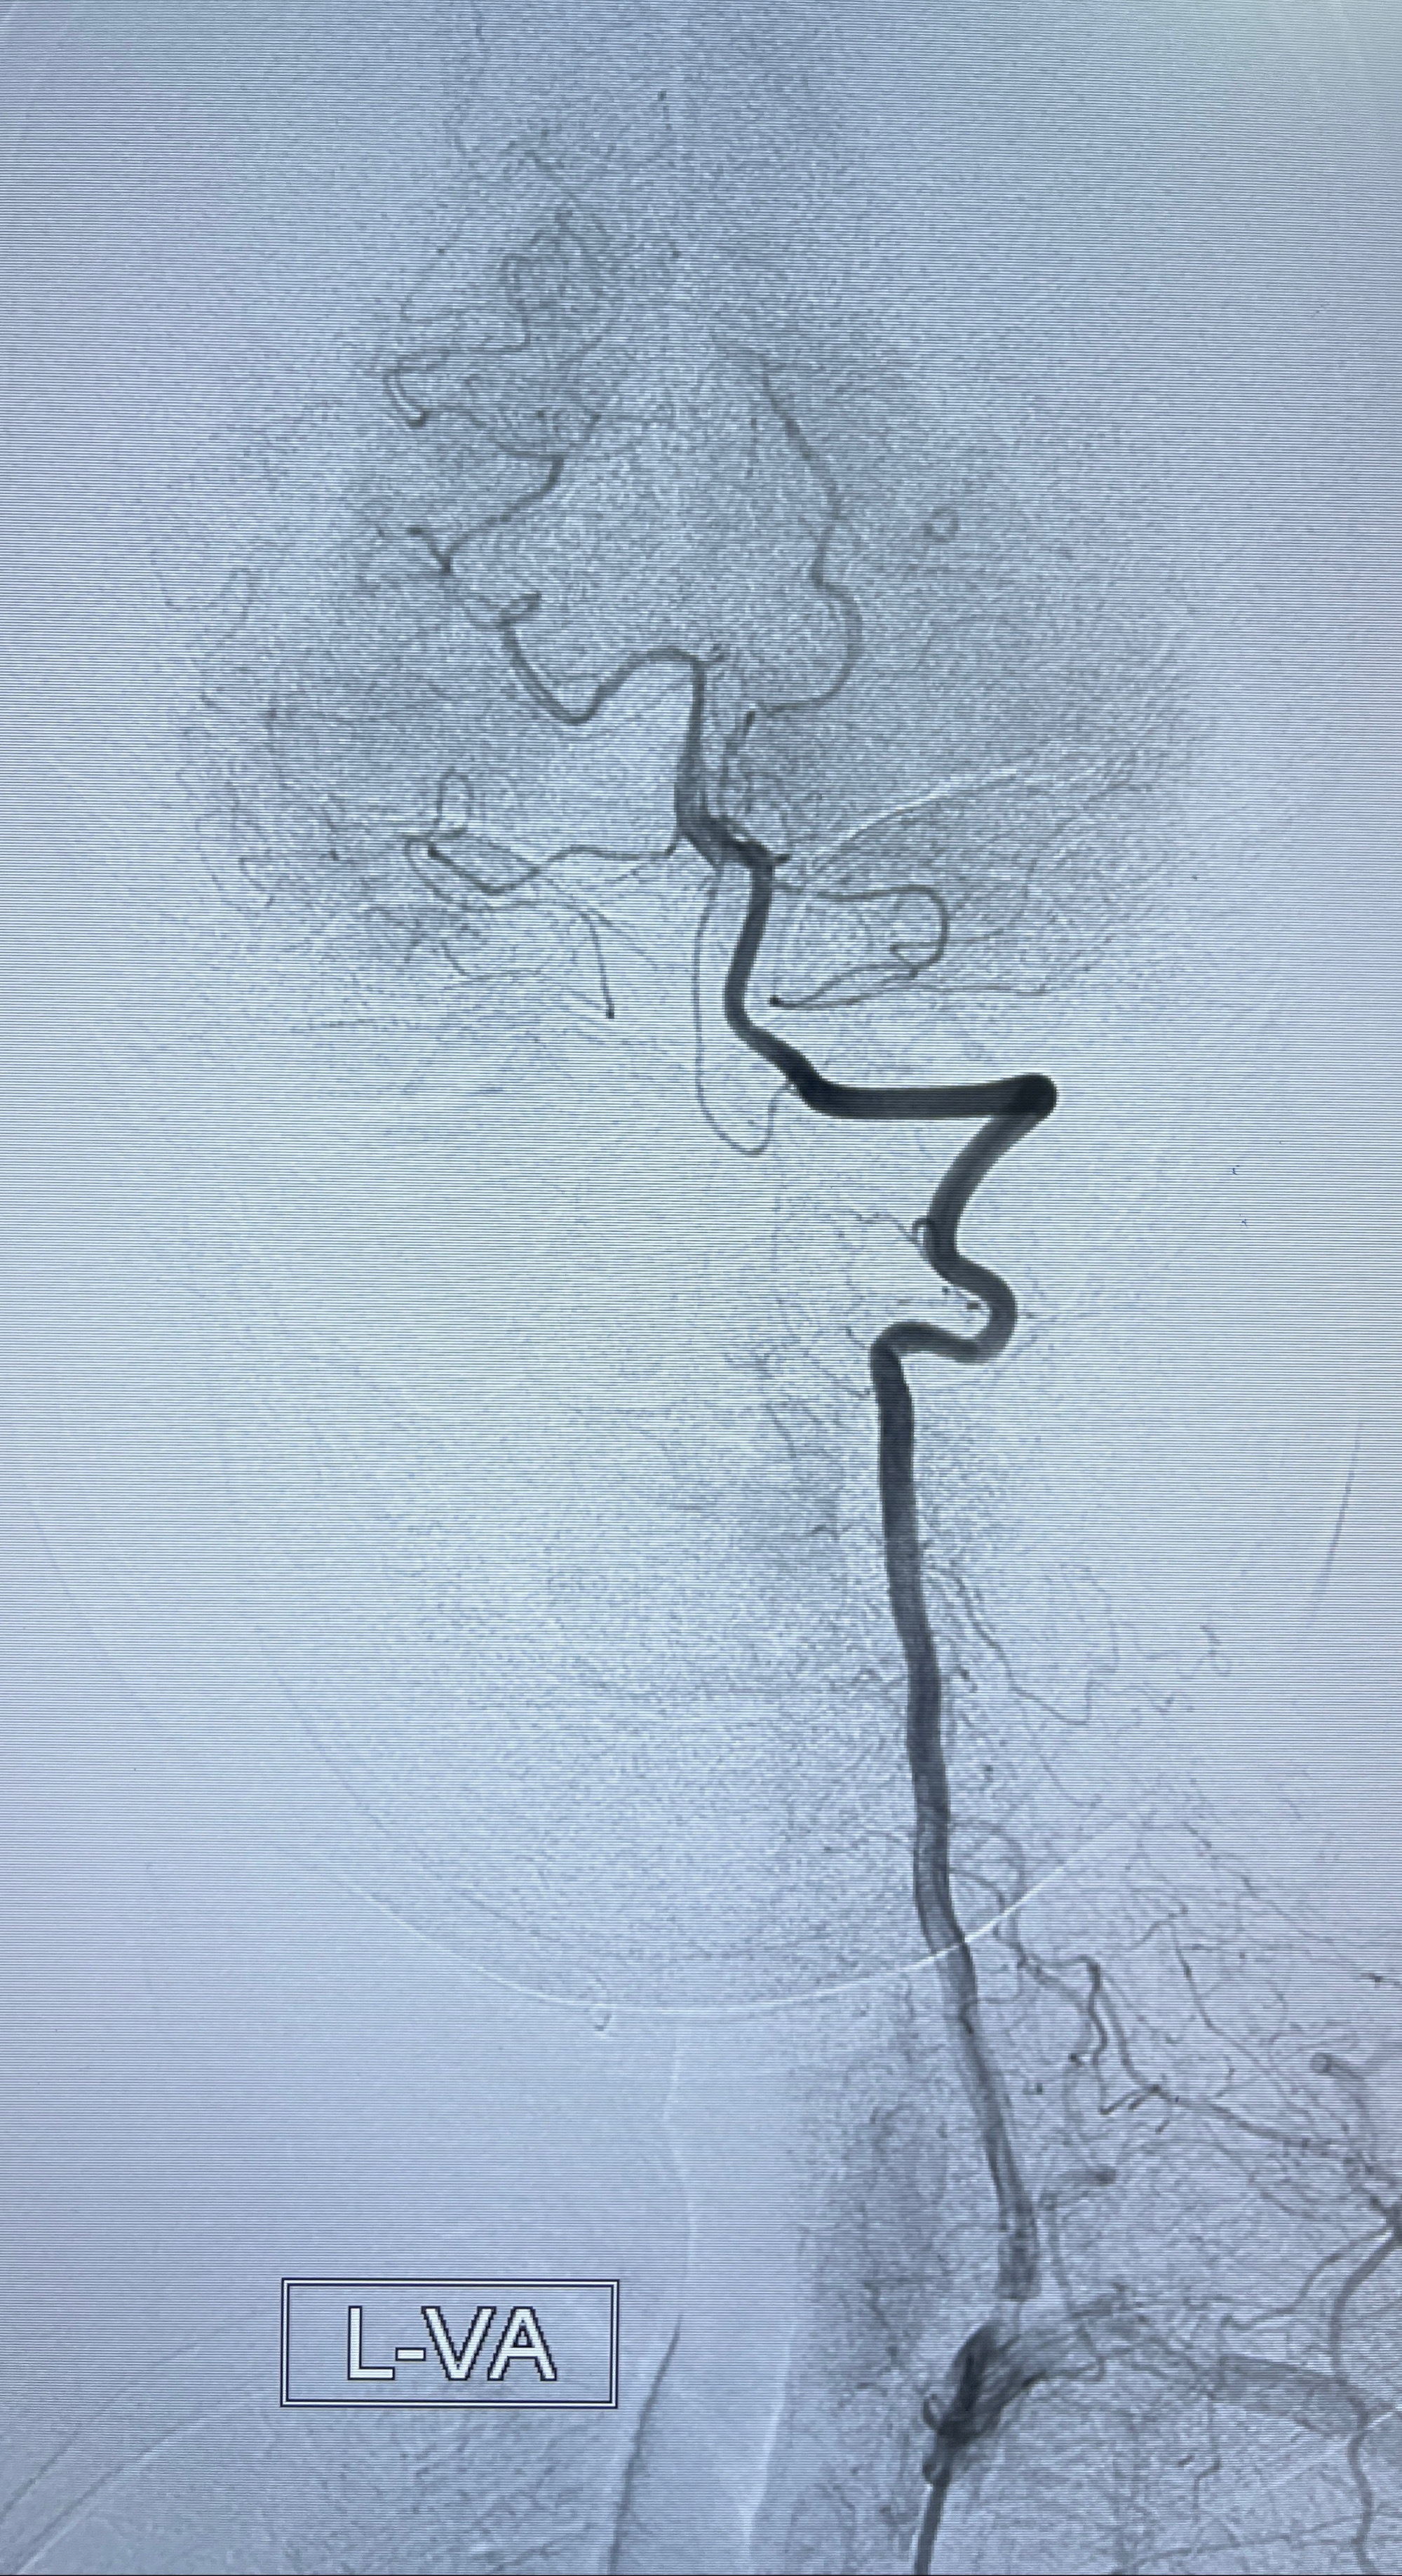

2023-08-30DSA:左侧颈内动脉眼动脉动脉瘤,约3*9.2*7.3mm大小

2023-09-06全麻下行左侧颈眼动脉瘤

密网支架辅助栓塞